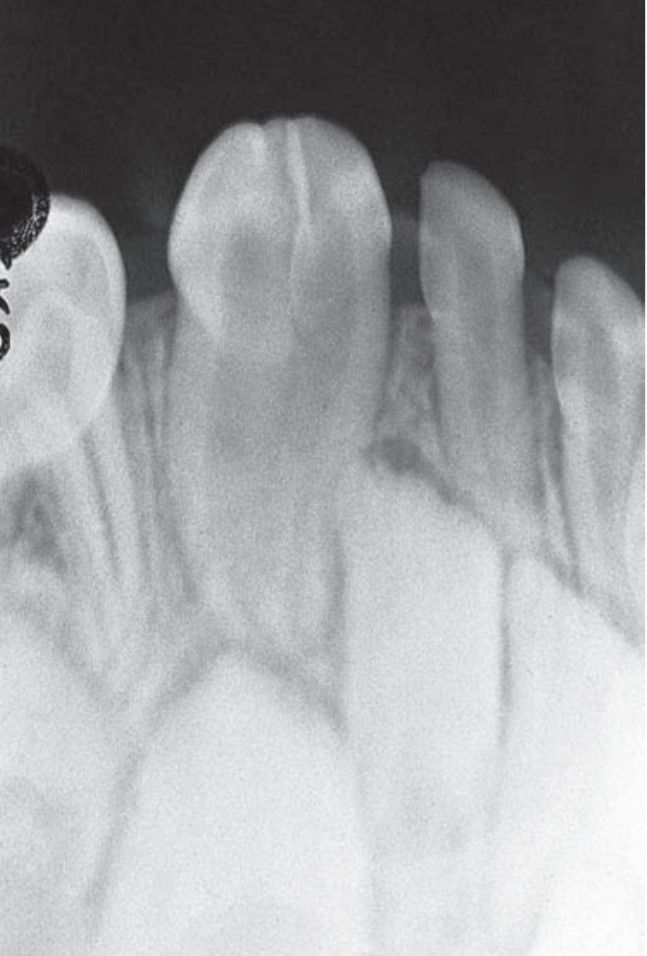

Fusion is the joining of two developing tooth germs, resulting in a single large tooth structure.

Fusion